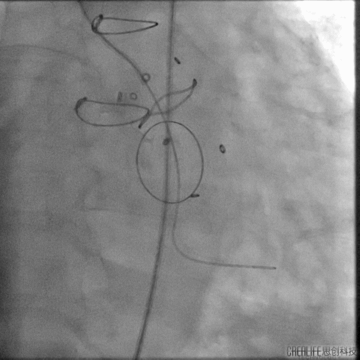

跨瓣建立轨道

主动脉瓣架植入

根据造影情况决定选择VenusA 23号瓣膜

主动脉瓣架释放

复查造影